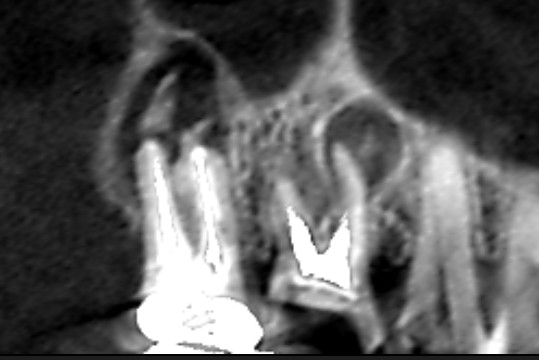

初診時のCT画像です。左端の歯が第二大臼歯、左から二番目の歯が第一大臼歯です。